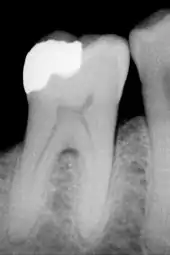

Détail d'une molaire humaine :

- En haut, l'émail composé principalement de la couche prismatique, et dans sa partie supérieure la couche finale sans bâtonnets. En bas, la dentine.